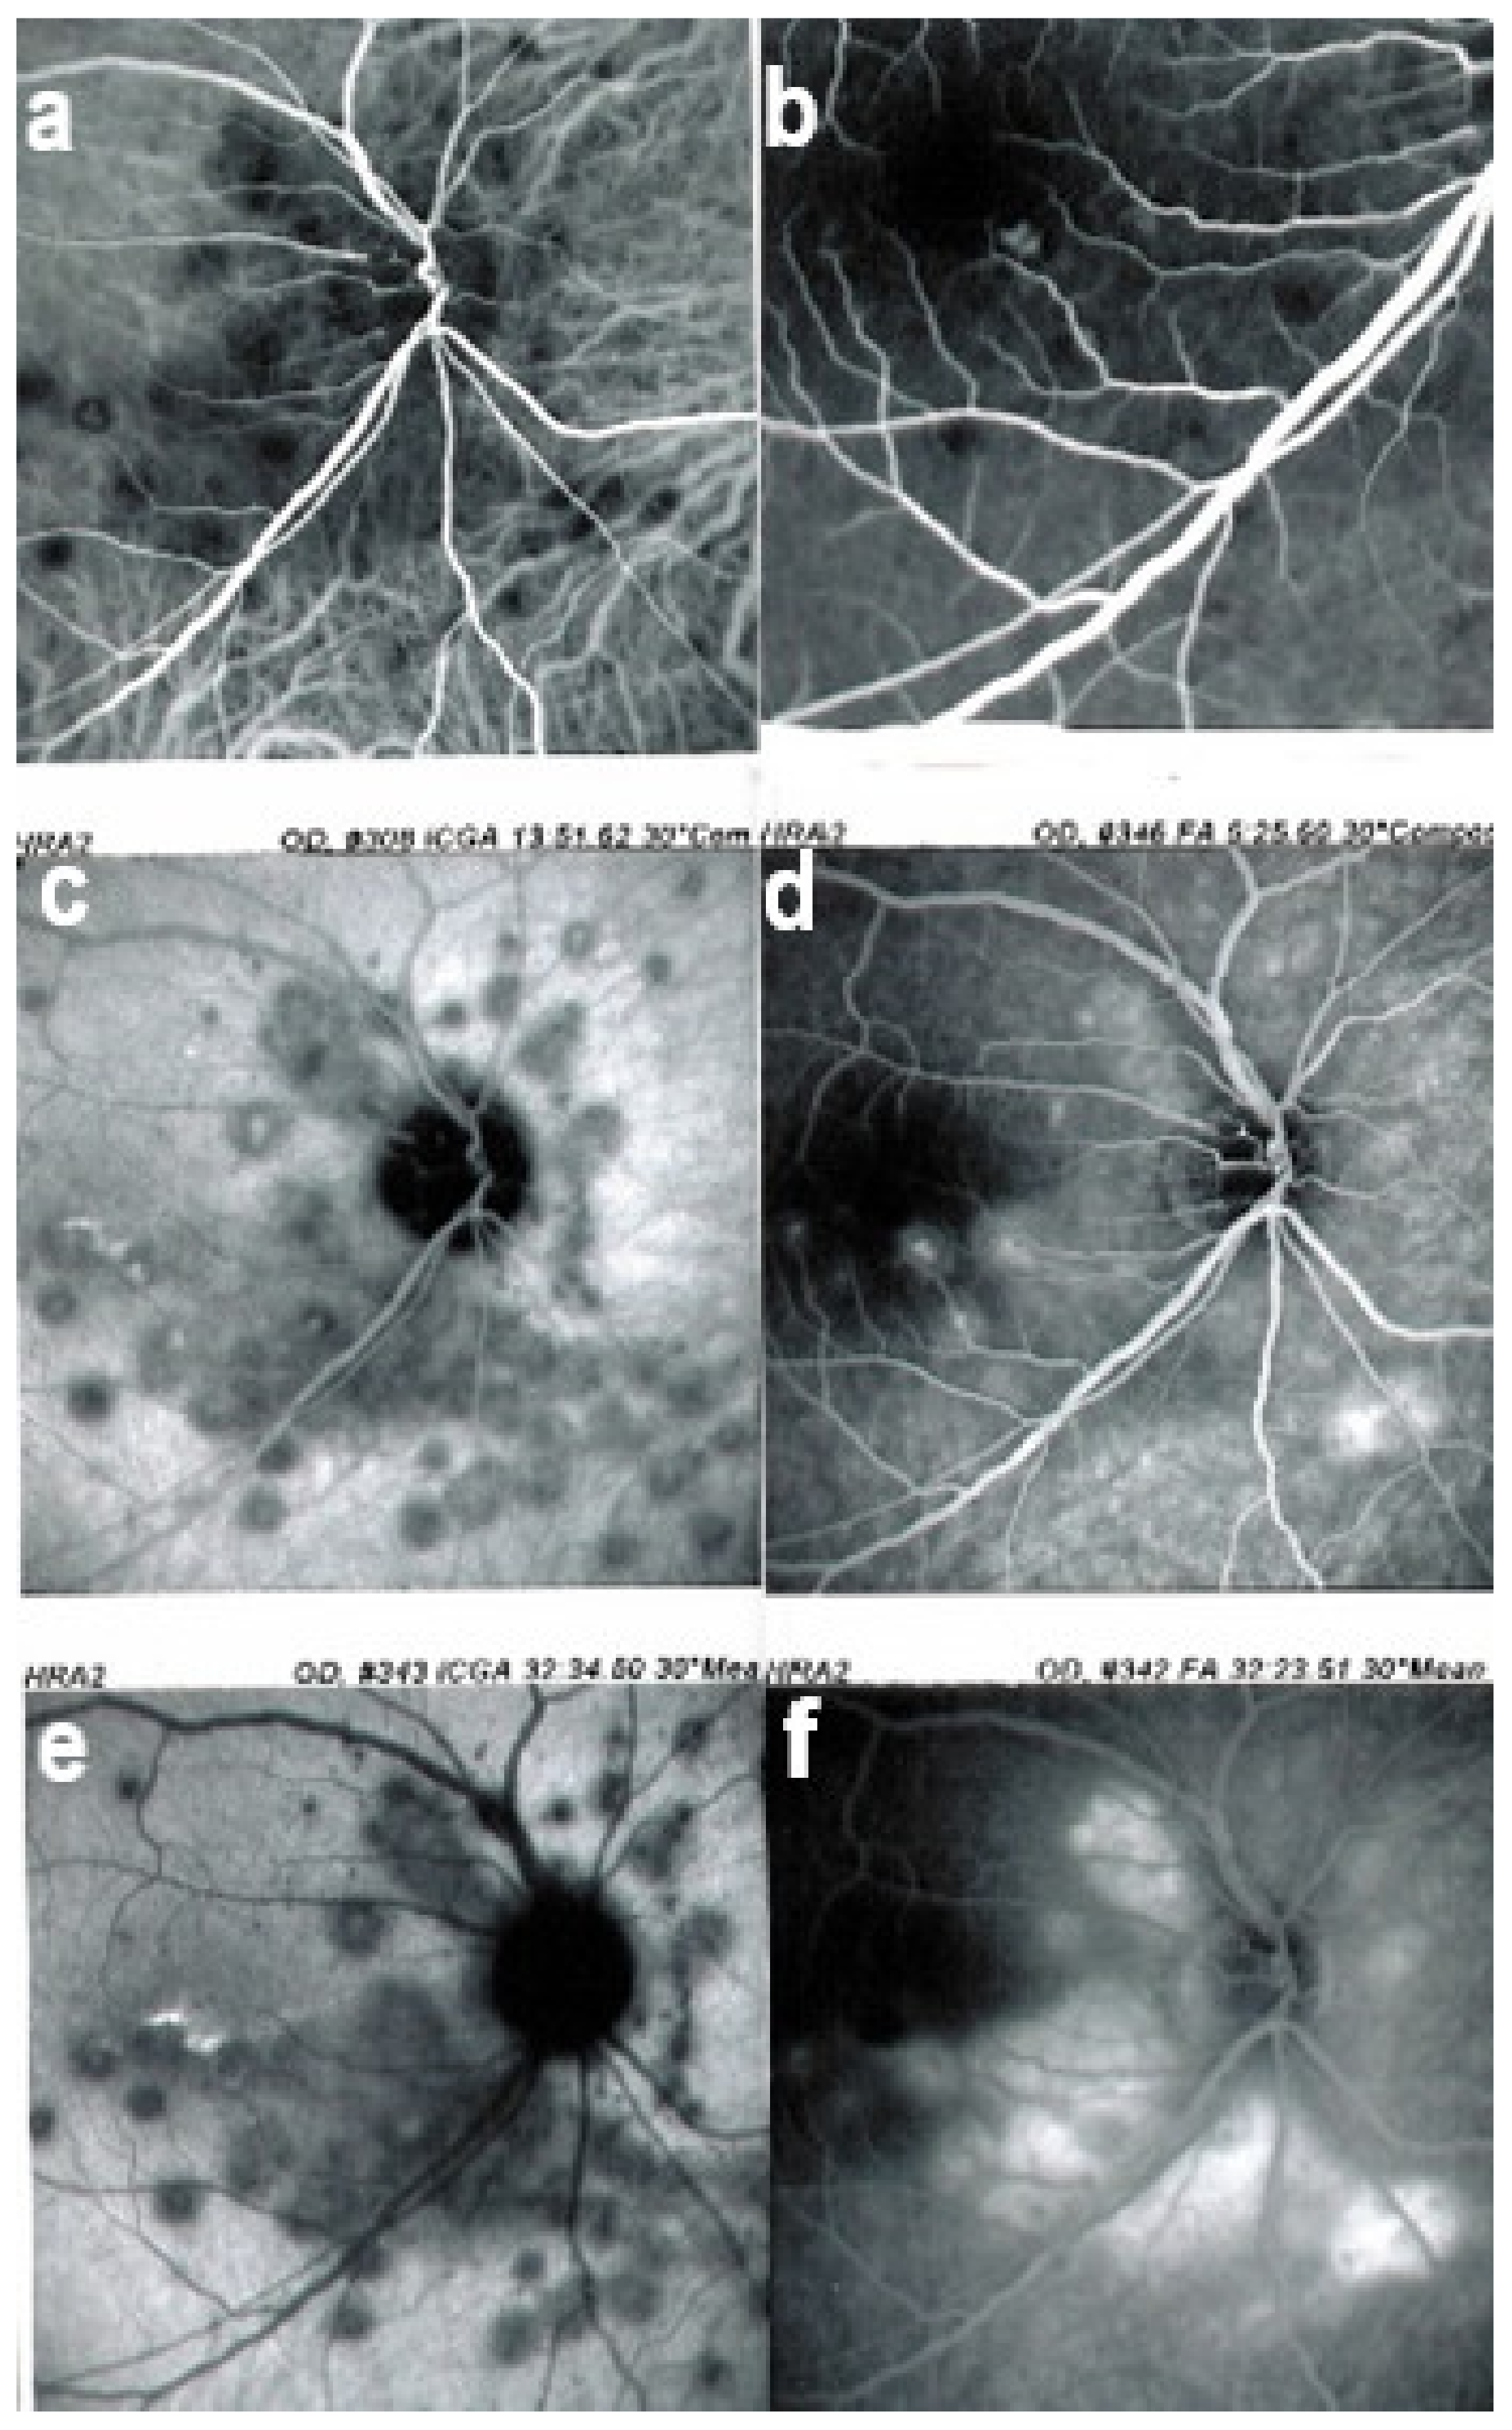

FA shows mainly signs of chorioretinal scaring associating by window effect (late sclera hyperfluorescence due to staining) to masking effects where there is pigment clumping. In the active phase, FA may show faint late hyperfluorescence in areas corresponding to ICGA, hypofluorescent dark areas corresponding to new lesions. In case of severe hypoperfusion of the choriocapillaris, bright FA late hyperfluorescence (retinal and subretinal staining) can occur as for APMPPE/AMIC (Figure 16). The use of FA is, however, of little contribution to assess and follow active disease.

Figure 16.

MFC. Parallel time sequence of ICGA (a,c,e) and FA (b,d,f) during recurrence. Top pair (a,b) show early ICGA and FA frames, showing extended hypofluorescent area on ICGA, while FA is practically normal. Middle pair (c,d) of images show intermediate phase of ICGA and FA (about 10 min) with more extended and well-visible zones of hypofluorescent choriocapillaris nonperfusion on ICGA, while FA shows leakage and staining. Bottom images (e,f) corresponding to late ICGA hypofluorescent areas causing retinal ischaemia and reactional retinal vessel hyperpermeability following the same mechanism as in APMPPE/AMIC.